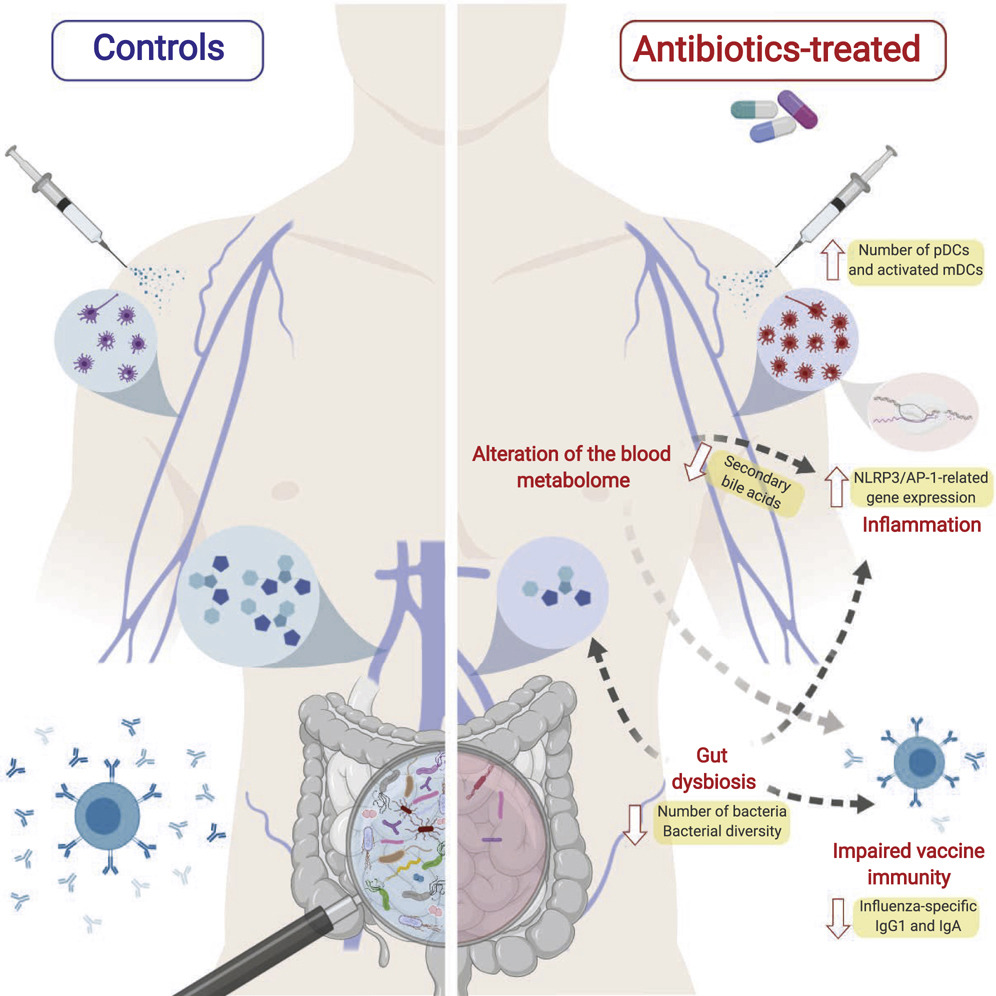

영양불균형과 장내세균 불균형을 바로잡아 장내 유익균을 복원하면 면역력 균형과 체력이 건강해져 백신 접종 후 가슴두근거림 증상 회복에 도움이 된답니다.

복합유익균과 유산균을 같이 먹어 장내세균 다양성을 복원하면 면역력 균형이 건강해져 독감(인플루엔자), 코로나19 백신 부작용도 없고 설령 코로나19나 독감에 감염되어도 무증상 또는 가벼운 증상만 겪고 완치된다는 연구가 있습니다.

장내세균 다양성을 유지하면 항체의 다양성이 합성돼서 다양한 항원인 백신을 맞아도 백신 부작용이 없거나 가볍다고 합니다

연구자들은 전해질균형, 영양균형, 장내세균 균형을 바로잡아주면 백신 접종 후 부작용 예방과 가슴두근거림, 우울증, 공황장애, 범불안장애, 불안증 등 예방과 회복에 도움이 되고 백신 접종 후 가슴통증 등 다양한 백신 부작용 회복에도 도움이 된다는 것은 상식이고 물리학이며 진리라고 연구자들은 강조합니다.